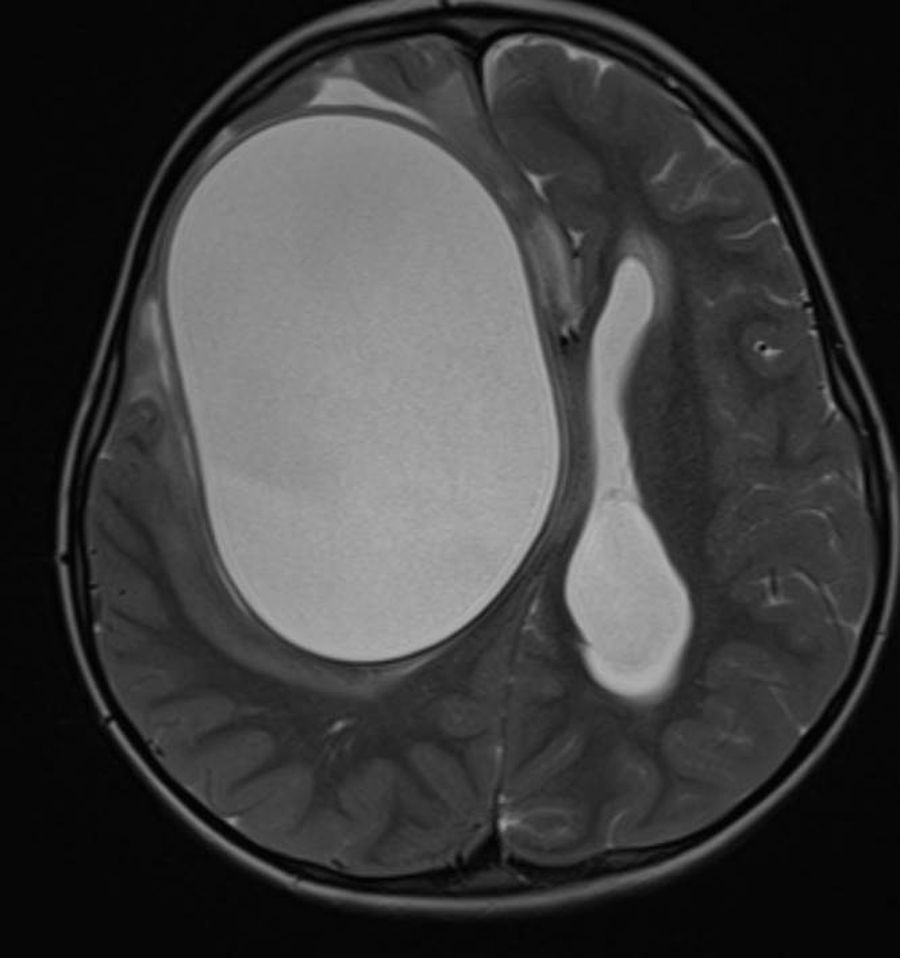

— Во время обследования были обнаружены небольшие новообразования в лёгких и громадная киста в головном мозге. Она занимала почти все правое полушарие и сдавила мозг так сильно, что что между мозговым плащом и черепом осталось не больше двух миллиметров, — сообщили в Новосибирской областной клинической больнице.

Нейрохирурги очень аккуратно, с использованием методики водной диссекции, высвободили кисту и извлекли её из черепной коробки, не повредив. Сдавленные участки мозга встали на место. Операция длилась несколько часов.